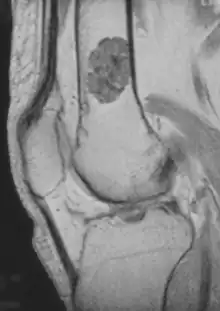

- X-ray – On plain film, an enchondroma may be found in any bone formed from cartilage. They are lytic lesions that usually contain calcified chondroid matrix (a "rings and arcs" pattern of calcification), except in the phalanges. They may be central, eccentric, expansile or nonexpansile.

Differentiating an enchondroma from a bone infarct on plain film may be difficult. Generally, an enchondroma commonly causes endosteal scalloping while an infarct will not. An infarct usually has a well-defined, sclerotic serpentine border, while an enchondroma will not. When differentiating an enchondroma from a chondrosarcoma, the radiographic image may be equivocal; however, periostitis is not usually seen with an uncomplicated enchondroma.